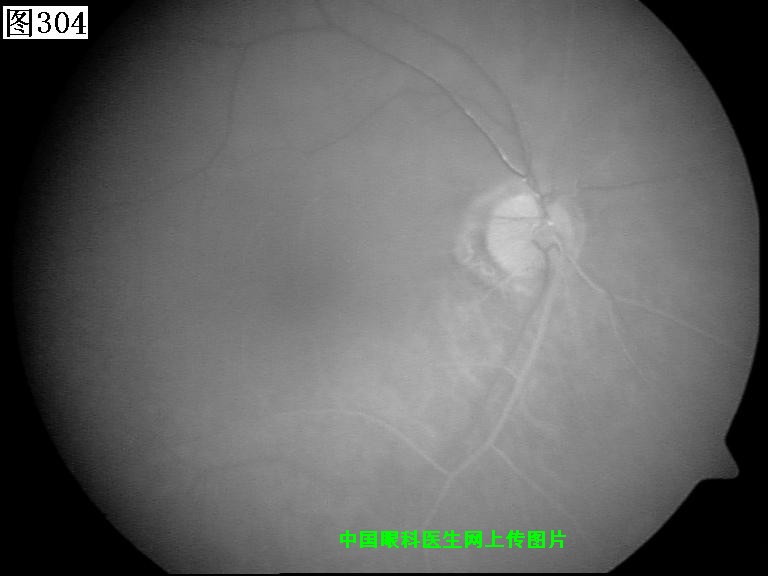

301 302 303 304